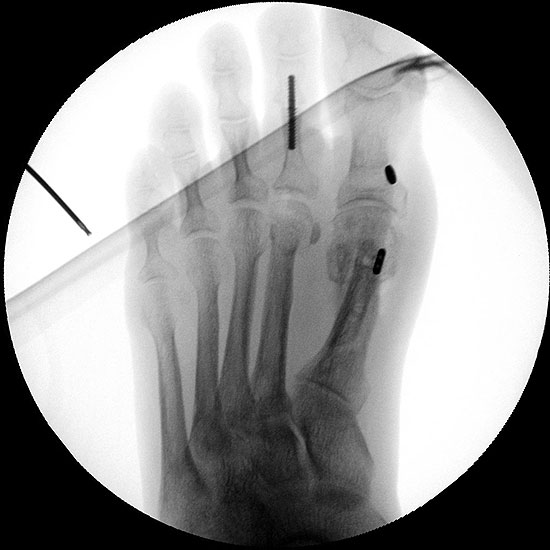

Die dorsoplantaren Röntgenaufnahmen zeigen eine Open-wedge Technik mit der normalerweise ein erhöhter intermetatarsaler Winkel gut zu korrigieren ist (Abbildung 3). Die Wirksamkeit einer Basisosteotomie ist umso größer, je proximaler diese durchgeführt wird. Je weiter distal die Osteotomie, umso geringer die Korrektur. Auf den postoperativen Bildern ist der distal unverändert große Abstand zwischen Metatarsale I und Metatarsale II erkennbar, bei gleichzeitiger Subluxation des Großzehengrundgelenks und dezentrierten Sesambeinen. Darüber hinaus finden sich initiale degenerative Veränderungen im Großzehengrundgelenk. Klinisch bestand eine hohe Weichteilspannung, bei verkürzter Extensor- und Flexor hallucis longus Sehne.  Daher wurde ein verkürzendes Verfahren zur Revision gewählt (Abbildung 4). Die Lapidusarthrodese stellt ein sehr zuverlässiges Verfahren zur Behandlung von Hallux valgus Rezidiven dar 9. Die Fusion des Tarsometatarsale-I-Gelenks kombiniert Stabilität mit einem hohen Korrekturpotenzial. Aufgrund der verfahrensimmanenten Verkürzung des ersten Strahls und der in diesem Fall bereits präoperativ vorhandenen Transfermetatarsalgie wurde die Entscheidung für eine verkürzte Weil-Osteotomie am zweiten bis fünften Strahl gefällt. Die Kombination beider Verfahren führte zu einem homogenen Metatarsale-Index und zu einer gleichmäßigen plantaren Druckverteilung 10. Die Hallux valgus interphalangeus Fehlstellung wurde mit einer Akin-Osteotomie korrigiert.